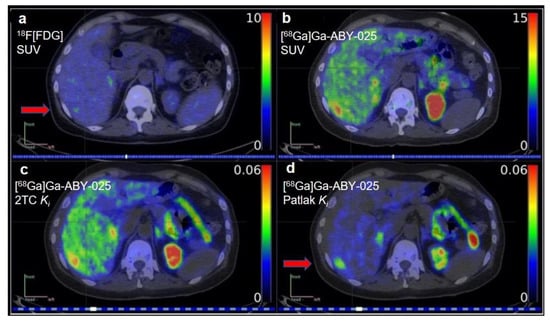

The second generation Affibody® molecule, ABY-025, has been improved by further modification of the nonbinding surface of ZHER2:342, and it can bind selectively to HER2 receptors with higher thermal stability and hydrophilicity than ZHER2:342 []. 68Ga-labeled affibody ABY-025 has also been investigated as an HER2-targeted imaging agent []. The Phase I clinical study of [68Ga]Ga-ABY-025-PET/CT in the detection and quantification of HER2 expression demonstrated high stability, fast blood clearance, and high reproducibility of the radiotracer []. In this study, kinetic modeling was used to quantify tracer uptake. Tracer kinetic models are the mathematical models that describe the time-varying distribution of radiotracers in the body []. Compared with SUV, kinetic modeling may provide a more accurate quantification of the tracer uptake in organs of interest []. Kinetic modeling may impact precision medicine through better estimations for the dosing of therapeutic agents, a more accurate dosimetry for radioligand therapies, and more accurate estimations of adverse events in nontarget organs. Alhuseinalkhudhur et al. explored kinetic modeling to analyze the relationship between the rates of [68Ga]Ga-ABY-025 uptake and HER2 expression in the tumor []. Sixteen patients with metastatic breast cancer underwent dynamic [68Ga]Ga-ABY-025-PET/CT imaging from 0–45 min postinjection. To test the reproducibility of [68Ga]Ga-ABY-025, 5 of the 16 patients underwent two PET scans with [68Ga]Ga-ABY-025. An [18F]FDG-PET examination was performed within 14 days prior to the first [68Ga]Ga-ABY-025-PET for all these patients. Parametric images of tracer delivery (K1), irreversible binding (Ki), and SUVs were calculated. Two-tissue-compartment (2TC) model and Patlak analyses were both used to create parametric images. The results showed that the Ki values agreed very well with the volume-of-interest (VOI)-based gold standard (R2 > 0.99, p < 0.001). SUVs in metastases at 2 h and 4 h post-injection were highly correlated with Ki values derived from both the 2TC model and Patlak methods (R2 = 0.87 and 0.95, both p < 0.001). High retest reliability was shown by the parametric image-based Ki values (Pearson’s r ≥ 0.92, n = 5). Parametric imaging provided good visualization and mitigated nonspecific background uptake in the liver (Figure 1). This study provided the proof-of-concept testing of tracer kinetic modeling in clinical imaging. Kinetic modeling could be very useful in quantifying tracer uptake in small metastatic lesions in organs where high background activity could be present.

Figure 1.

Patlak Ki images of [68Ga]Ga-ABY-025 provided good visualization of liver metastases and mitigated nonspecific background uptake in this organ relative to standardized uptake value (SUV) images. (a) [18F]FDG-PET, (b) [68Ga]Ga-ABY-025-PET, (c) parametric images of 2-tissue compartment (2TC) Ki, and (d) Patlak Ki in a breast cancer patient with multiple small liver metastases in the same patient. (Reprinted from Ref. []).